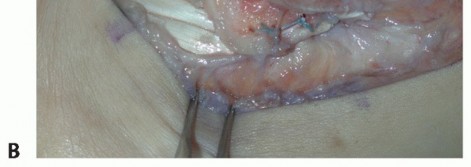

TECH FIG 1 • A. Intraoperative photograph of a left ankle (lateral approach) shows the peroneal tendons subluxing anteriorly (brevis is the gray arrowhead , longus is the white arrowhead , SPR is the black arrow). B. The peroneal tendons have been retracted anteriorly by the Penrose drain. Elevation of an anterior-based periosteal flap (outlined by dots) from the fibular groove has been completed. The black arrow shows the remnant of the SPR posteriorly. C. The tendons are relocated, after a groove-deepening procedure, into the recreated groove. The white dots outline the anteriorly based periosteal flap. It is then brought over to the posterior remnant of the SPR (black arrow). D. The flap is sutured to the remnant SPR with nonabsorbable sutures, completing the superior peroneal retinaculoplasty. |

| Reduce the peroneal tendons and use the periosteal flap to contain the tendons, with the visceral side of the periosteum facing the tendons (TECH FIG 1C). | |||

| Suture the flap to the posterior remnant of the SPR with a series of 3-0 polybraided nonabsorbable sutures (TECH FIG 1D). | |||

TECH FIG 1 • A. Intraoperative photograph of a left ankle (lateral approach) shows the peroneal tendons subluxing anteriorly (brevis is the gray arrowhead , longus is the white arrowhead , SPR is the black arrow). B. The peroneal tendons have been retracted anteriorly by the Penrose drain. Elevation of an anterior-based periosteal flap (outlined by dots) from the fibular groove has been completed. The black arrow shows the remnant of the SPR posteriorly. C. The tendons are relocated, after a groove-deepening procedure, into the recreated groove. The white dots outline the anteriorly based periosteal flap. It is then brought over to the posterior remnant of the SPR (black arrow). D. The flap is sutured to the remnant SPR with nonabsorbable sutures, completing the superior peroneal retinaculoplasty.